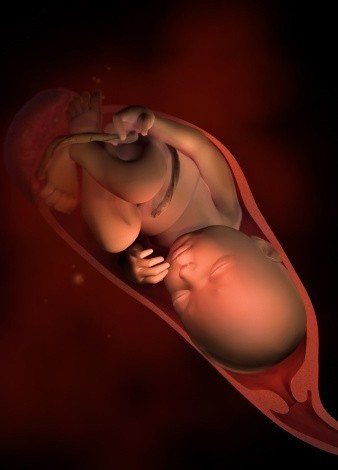

第十个月

胎宝宝身长约50cm,体重约3500g。胎宝宝已经发育成熟,要出生啦。